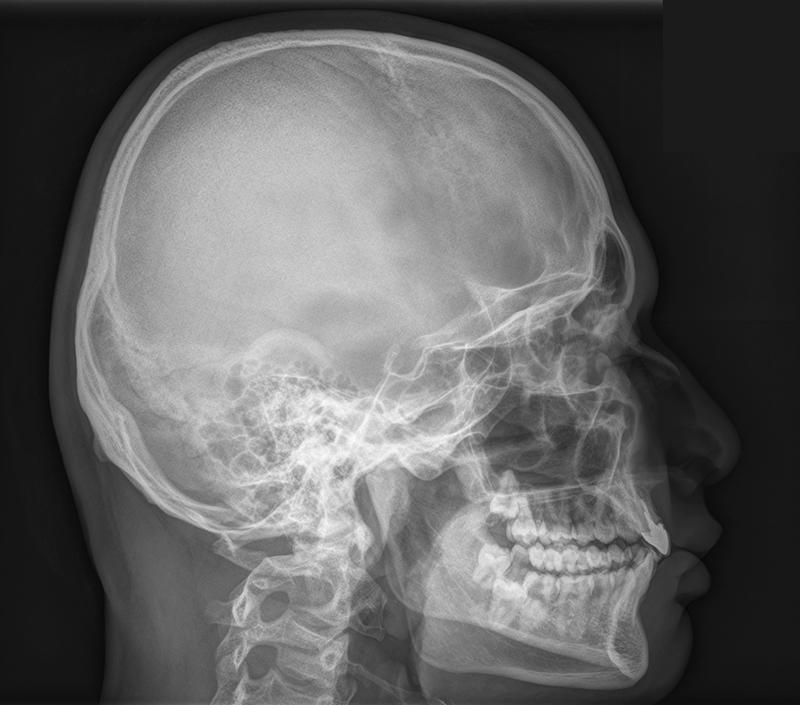

По словам следователей, между подростками вспыхнула ссора, и один из них схватил музыкальный инструмент. Пострадавшего прооперировали — у него перелом черепа и гематома.